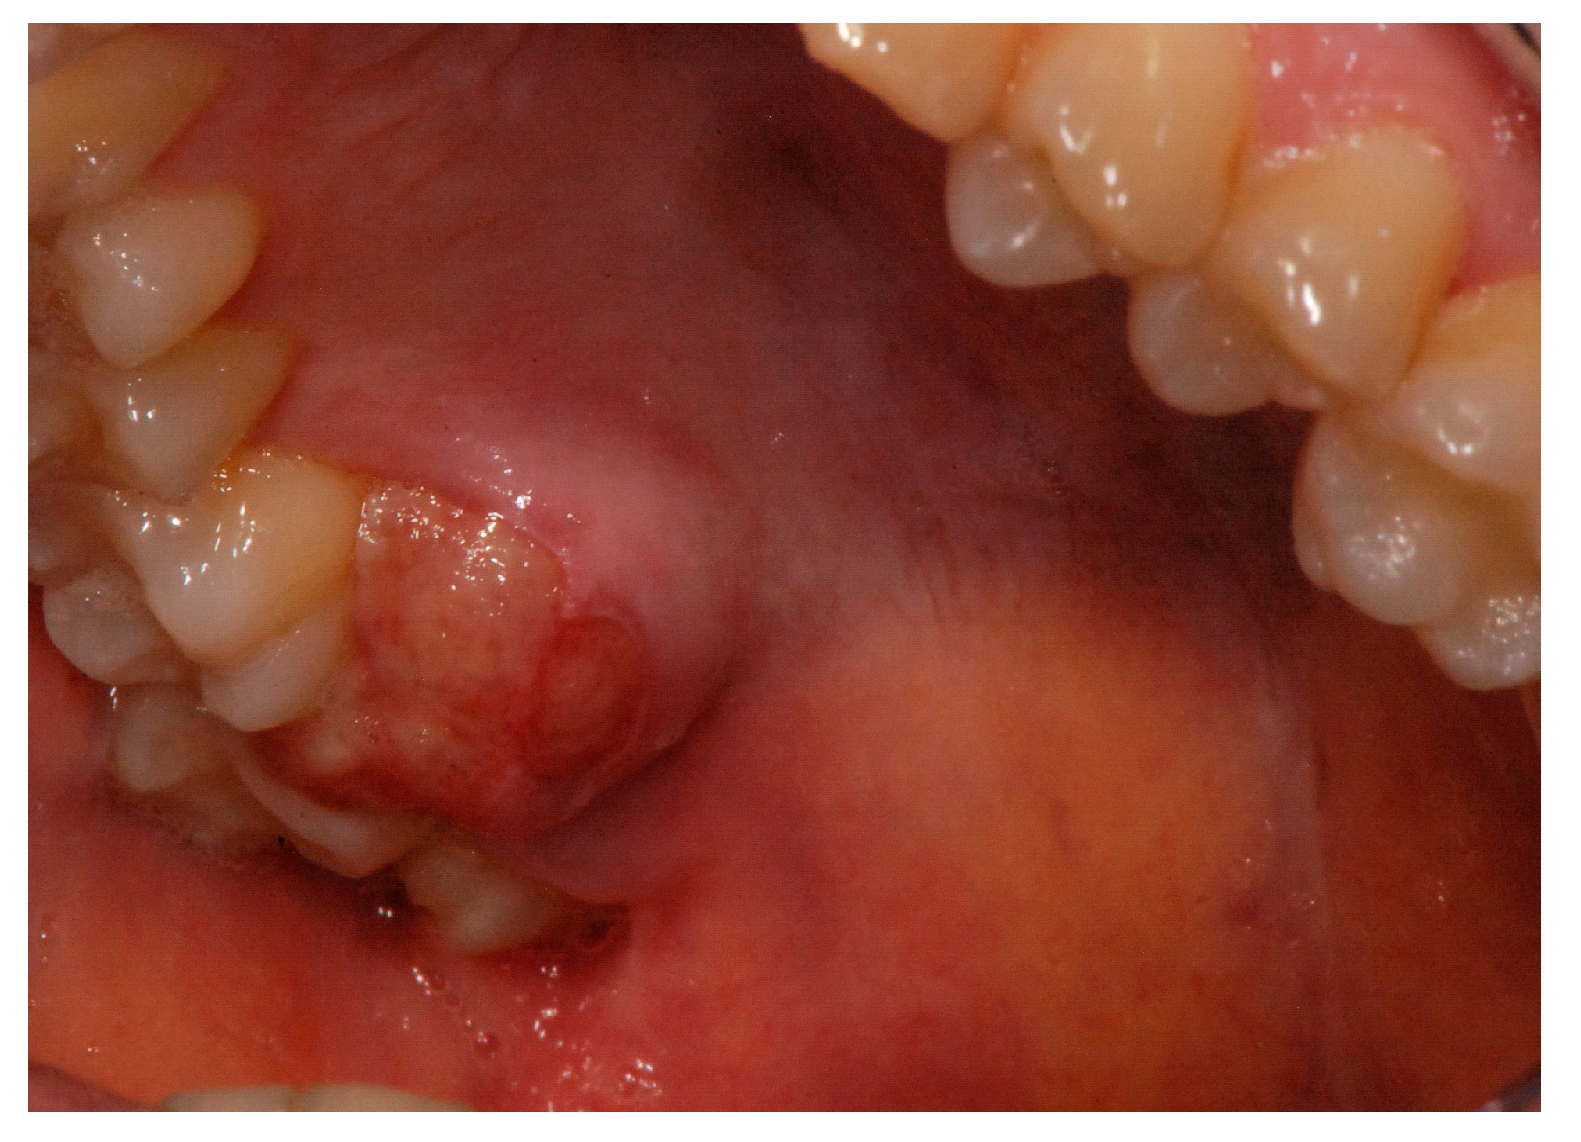

Oral Leiomyosarcoma or Low-Grade Myofibrosarcoma: Report of a Challenging Differential Diagnosis †